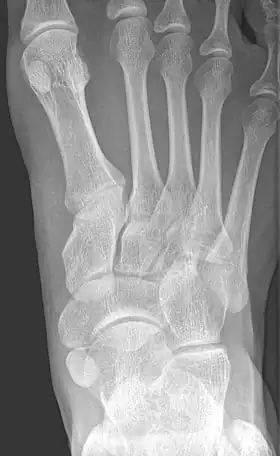

Radiographie du pied montrant un os naviculaire accessoire | ||

Un os naviculaire accessoire est un os accessoire du pied qui se développe parfois anormalement devant la cheville vers l'intérieur du pied. Cet os peut être présent dans environ 2 à 14 % de la population générale et est généralement asymptomatique[1],[2],[3]. Lorsqu'il est symptomatique, une intervention chirurgicale peut être nécessaire.

Les radiographies sont généralement commandées pour confirmer le diagnostic. S'il y a une douleur ou une inflammation en cours, une IRM ou d'autres tests d'imagerie avancés peuvent être utilisés pour évaluer davantage la condition.